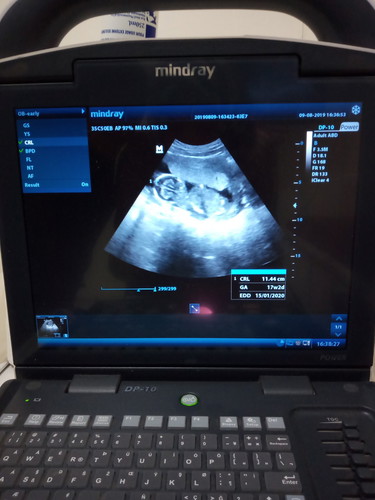

bunda mau tanya ini kehamilan pertama saya kenapa iyaa itungan kehamilan harusnya sekarang 16 week tapi tadi sore di usg kehamilan saya sekarang 17 week itu gimana iyaa,,??

Ya g gimana gimana bund Wajar banget itu Apalgi cm selisih seminggu USG kan ngitung usia dr berat janin juga bund Nanti cek selanjutnya, itungannya bisa sama, bisa kurang, bisa lebih Pkknya ikuti hitungan HPHT aja